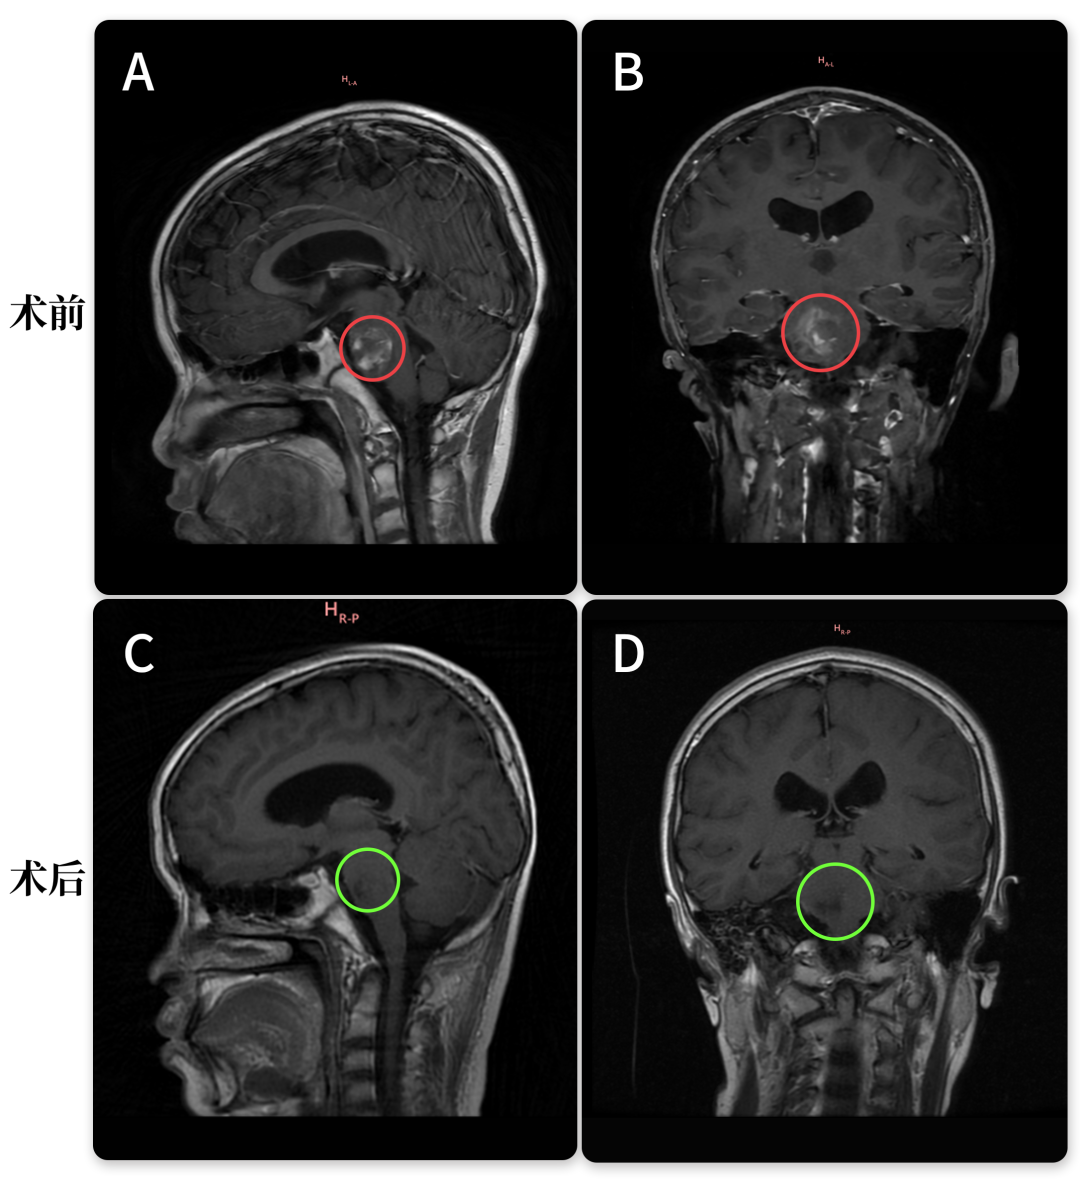

12岁男性患儿因频繁头痛恶心症状就诊,经磁共振检查发现脑干海绵状血管瘤。病灶位于脑干关键区域,初期经北京医院专家评估建议采取保守观察方案,患儿家属接受该建议并带患儿回家观察。

经过半年观察期,患儿出现双腿无力症状,复查核磁共振显示血管瘤少量出血。再次选择保守治疗方案后,症状暂时缓解。4个月后患儿出现左手无力表现,经当地及北京医院复查确诊为血管瘤二次出血。北京医疗团队建议手术治疗,但告知可能存在视神经损伤、吞咽功能障碍、语言能力受损及瘫痪等术后风险。

面对手术风险,家属寻求第二诊疗意见,联系巴特朗菲教授进行远程咨询。经评估,巴特朗菲教授认为该手术风险较低,术后恢复正常功能可能性较大。在巴特朗菲教授来华医疗交流期间,家属决定接受手术治疗。

手术完成后,患儿在重症监护室观察一晚,次日上午转回普通病房。术后患儿意识清醒,语言功能和沟通能力保持完整,四肢活动能力未受影响,面部对称无歪斜,视神经功能完好。术后初期患儿即表达购买自行车的愿望,显示其积极乐观的心态。

术后恢复情况优于预期,患儿行走能力、语言功能及智力水平均保持正常状态。家属对选择巴特朗菲教授进行手术的决定表示充分肯定。

术后6个月随访复查时,核磁共振显示脑干区域存在异常信号,初步考虑海绵状血管瘤可能,引发家属担忧。经巴特朗菲教授远程随访确认,该异常信号实为含铁血黄素残留,属于巨大出血性内生性脑干病变的正常术后表现,并非活动性海绵状血管瘤复发或残留。

术后8个月随访显示,患儿身高增长,体质增强。巴特朗菲教授亲自评估后认为患儿状态良好,无需过度担忧。两次随访结果均显示阳性预后,家属对治疗结果表示满意。